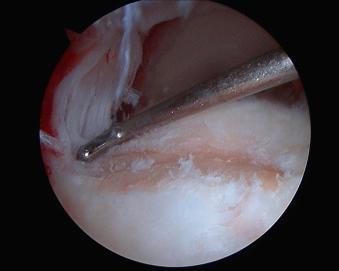

Glenohumeral Joint

The range of motion and stability of the shoulder are examined under anesthesia prior to arthroscopic glenohumeral joint inspection. Intra-articular lesions are not visualized during open repair, precluding an adequate comparison with arthroscopic findings. Most arthroscopic studies report abnormalities, such as focal synovitis, partial biceps tendon tears, arthritic changes in the humeral head or glenoid, labrum tears, and loose bodies. It is uncertain whether these intra-articular lesions arise because of the cuff tear or are merely part of the normal aging process. Arthroscopic findings in older patients with irreparable tears include arthritic changes, synovitis, and biceps tendon tears. Not surprisingly, these findings occur with a higher frequency than in patients with partial or complete rotator cuff tears that are reparable. Overall, glenohumeral joint abnormalities occur in 12.5% of patients and include osteoarthrosis, biceps tendon tears (partial or complete), labrum tears, labrum separations (superior labrum from anterior to posterior [SLAP] lesions), synovitis, and capsular contracture. During arthroscopy of the glenohumeral joint, full-thickness tears can be visualized and marked with a spinal needle if required ( Fig. 12.14 ). The anterior portal is often established here to palpate structures and to view the posterior structures prior to entering the subacromial space. Subscapularis tears are addressed later in the chapter, but repair can be initiated or completed in the glenohumeral space.

FIGURE 12.14, Full-thickness supraspinatus tear seen from the articular side in a right shoulder.